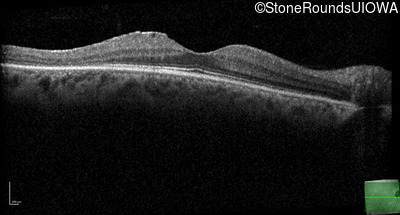

Optical Coherence Tomography - Left - 20/25

Exemplar / OCT Stack